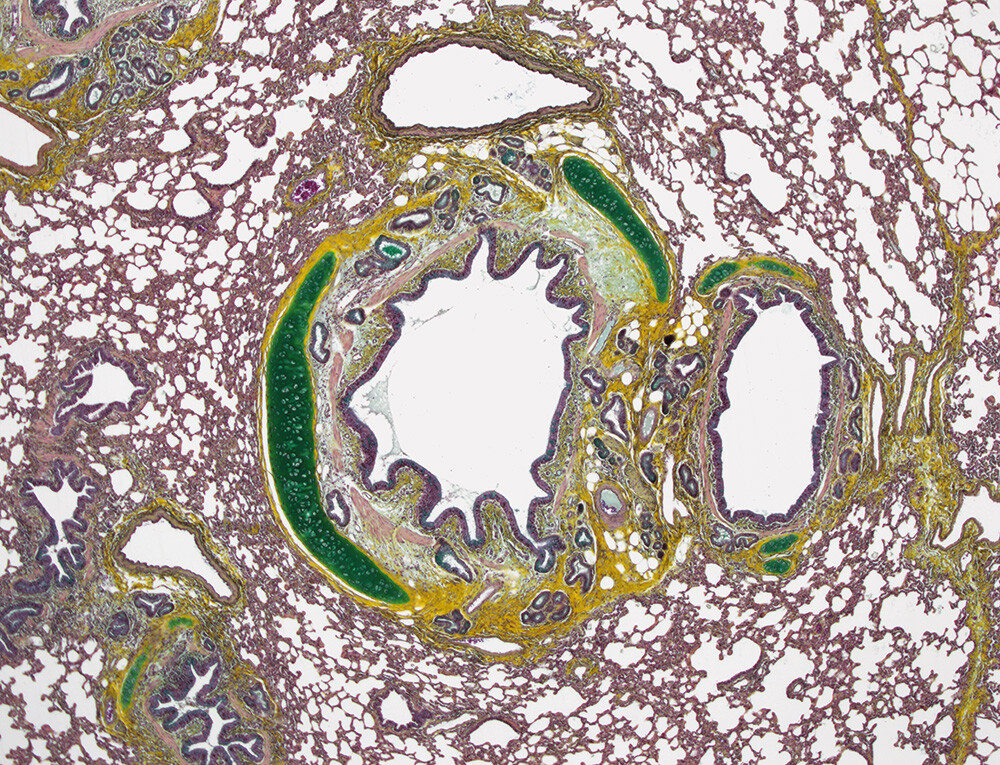

Identifying and classifying post-intervention microscopic vascular changes are key to understanding the acute and chronic effects of a surgical intervention in both vascular structures and the device. The composition of many medical devices is not amenable to paraffin embedding, so resin embedding plays an important role in the pathology evaluation. At Veranex, we have the specialized technical lab expertise and equipment to perform resin embedding, something we consider a key differentiator for our practice.

Again, imaging contributes to the assessment by providing spatial context. Non-destructive methods such as microCT, which we have available to us via key partners, reveal insights not available through the conventional pathological diagnostic process. We also use scanning electron microscopy to characterize developments such as calcification on the device.